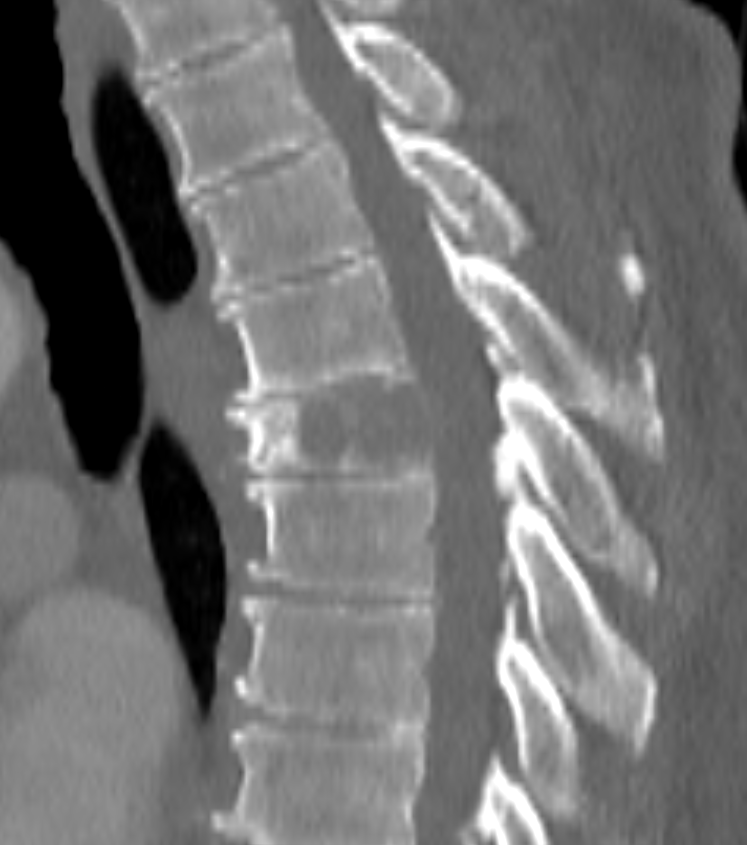

- CT:

- Higher sensitivity for detecting small lesions

- Useful for assessing cortical destruction and soft tissue extension